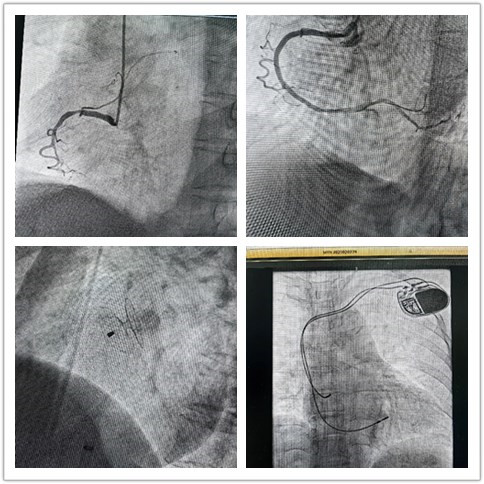

“组团式”帮扶队员—心内科邓纪钊,立即组织指导多学科团队开通胸痛绿色通道,有条不紊进行急诊术前相关检查,诊断为急性下壁心肌梗死。绕行病房,直达介入手术室,仅用32分钟顺利开通血管,患者转危为安,预后良好。

用“心”医治,点亮生命,是医者的初心使命。借力“组团式”帮扶,镇安县医院心内科救治能力和水平不断提高,业务范围不断扩展,先后完成多例卵圆孔未闭封堵、永久性心脏起搏器植入、心律失常射频消融术等。县医院从2022年3月组建介入科至今,截至发稿,冠脉介入手术已逾1000例,急诊冠脉内介入治疗手术已过百例,无1例手术相关医疗事件发生。这是镇安县医院发展史上的里程碑,也是前行的新起点。相信在欧美视频